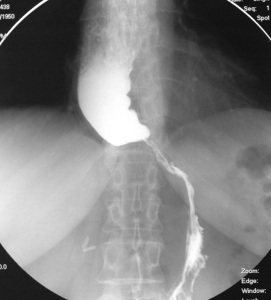

- рентгенологическое контрастное исследование – пациенту предлагают проглотить порцию контрастного вещества (сульфата бария), после этого делают серию рентгенологических снимков. По ним выявляют скорость перемещения сульфата бария по пищеводу и освобождения от него конечного участка пищевода;

- Рентгенография грудной клетки. Обследование начинается именно с данного исследования. В случае выявления на рентгенограмме тени расширенного пищевода с жидкостным уровнем назначается рентгенография пищевода, предполагающая предварительный прием бариевой взвеси. Если имеет место ахалазия кардии, то становится заметным сужение конечного отдела пищевода, а также расширение участка, располагающегося выше.

Основным критерием эффективности медикаментозного лечения является устранение симптоматики. Для определения эффекта опытным путем проводят рентгенологическое исследование с параллельным введением бария. Если бариевые взвеси нормально проходят по пищеводу, значит, лечение помогло.

У больных с кардиоспазмом при рентгенологическом исследовании выявляют усиление моторики пищевода с выраженными сегментарными сокращениями, при ахалазии кардии — снижение моторной активности пищевода (отсутствие первичной перистальтики в дистальных 2/3 пищевода).

Рентгенологическими признаками кардиоспазма являются расширение пищевода в той или иной степени с наличием «узкого сегмента» в терминальном его отделе. Стенки пищевода, в том числе и в суженной части, сохраняют эластичность. В расширенном пищеводе натощак определяется значительное количество жидкости.